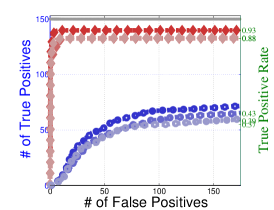

To understand the performance of this standard method, we present a small preview of our simulation study discussed later in Section 4. Briefly, we assume that each subject graph in group follows a small-world structure on nodes; in group , there are in addition 150 differential edges, meaning that and for all differential edges, . We generate data according to this model with time points and subjects in each group. Figure 1 illustrates the results of this standard approach as well as our new procedure, , which we will introduce later in Section 3. Part (a) gives ROC curves for the number of false positives verses true positives as each sequential test is rejected; parts (b) and (c) give the adjacency confusion matrix illustrating where the true and false positive as well as false negative edges are detected in the graph structure.

Our motivating simulation shows that the standard approach performs terribly in terms of both error control and statistical power. While the magnitude of the poor performance of this approach may seem astonishing, the poor performance should come as no surprise: The inferential procedure (e.g. test statistics) of the standard approach assume a one-level model that would be appropriate when the subject graphs are fixed and known or directly observed quantities. When these subject networks are unobserved, however, and must be estimated from finite data, these one-level test statistics are incorrect for our two-level problem. Specifically for two-level problems, the variance of parameters estimated by incorrectly assuming a one-level models is underestimated. For our problem, the extra source of variability arises from the graph selection procedure; we discuss challenges associated with this subsequently in Section 2.2. Incorrect variance estimates, however, are not the only problem with the standard approach: A more subtle problem arises from the fact that the proclivities of graph selection procedures for the Gaussian graphical model lead to biased estimates of the edge proportions, . As discussed in Section 2.3 and seen in Fig 1, graph selection false positives and false negatives do not occur at random throughout the network structure, leading to biased group level estimates.

Hence, the first term represents variability across subjects in group and the second term represents the variability associated with the selection procedure within subject , a quantity that we assume to be constant across subjects in each group . Consider now what happens if our true model follows this two-level Beta-Binomial model, but as with the standard approach, we use a one-level Binomial model and associated two-sample test statistic. The variance is thus underestimated and the test statistic is overoptimistic. Then, when inference is conducted for the population mean , using the incorrect Binomial model leads to inflated Type I error rates; this behavior has been well-documented (Weil, 1970; Liang and Hanfelt, 1994). Hence, failure to use the correct two-level model which accounts for the two levels of network variability partially explains the high error rates of the standard procedure observed in Figure 1.

In Figure 4 and Table 1, we present our main simulation results comparing to the two variations of our method and the standard approach for three network structures and Case I and II type differential edges. First for Figure 4, we report results in terms of operating characteristics averaged across 50 replicates with the number of true positives (y-axis) plotted against the number of false positives (x-axis) for each test statistic, rejected sequentially from largest to smallest in absolute magnitude. Overall, all of our methods and particularly yield substantial improvements over the standard approach in all scenarios.

Notice that both and =(RS,RP) share similar orderings of test statistics, and consequently similar ROC curves. Overall, methods that include random penalization yield major improvements in statistical power over those that do not. This indicates that the second popPSI challenge outlined in Section 2.3 is a significant contributor to the poor performance of the standard method. Recall our discussion of how graph selection errors at the subject stage occur non-randomly and hence bias our group-level estimates of . Our results empirically demonstrate that random penalization dramatically improves these biases, leading to less bias in our test statistics and hence improvements in both Type I and Type II error rates. Furthermore, in Case II scenarios where selection errors are moderate, the performance gap between any method containing over reduces compared to Case I scenarios where selection errors are more severe. Thus, the benefits of random penalization are greater when selection errors are more abundant. Confusion adjacency matrices illustrating the location of inferential errors for our methods shown in the supplemental materials also indicate that random penalization improves graph selection in cases where there are larger correlations between differential edges and common edges. Similar results hold for our high-dimensional study presented in the supplemental material.

Table 1, which accompanies Figure 4, gives the empirical true positive and false discovery rates (FDR) averaged over 50 simulation replicates when the Benjamini-Yekutieli (Benjamini and Yekutieli, 2001) procedure controlling the FDR at 10% is used to determine the number of tests to reject. First, notice that the observed false discovery proportion (FDP) of our procedure is not 10% on average, indicating that our method does not fully control the FDR. This occurs because we specifically simulate difficult and realistic fMRI scenarios with graph structures that severely violate irrepresentable-type conditions. In situations (not shown) where irrepresentable-type conditions are met that ensure graph selection consistency, our procedure as well as the standard method correctly control the FDR. As discussed in Section 2.3, in situations where graph selection errors occur with high probability, it is likely impossible to provably control the FDR, consistent with our empirical results. Yet even though does not fully control the FDR, our error rates are dramatically improved over the standard approach and other variations of our procedure.

Also in Table 1, observe that (RS,RP), which had similarly ordered test statistics to , has dramatically worse Type I error rates that do not come close to controlling the FDR. While (RS,RE) also does not control the FDR, the error rates are much improved over (RS,RP). These results demonstrate that using two-level models with the correct random effects test statistics are crucial to Type I error control. Recall from Section 2.2, that using the one-level Binomial model leads to an under-estimation of the variance term which in turn inflates test statistics and leads to an increase in false positives. Note also that the estimated FDP of is still a major improvement over that of (RS,RE). This occurs as the problem of graph selection errors induces both Type I and Type II errors. Hence, these results demonstrate the necessity of all three of our ingredients. Finally, observe that our error rates in Case II scenarios are better than those for Case I scenarios, again indicating that differential edges that are highly correlated with non-edges and common edges pose particular challenges for our popPSI problem. These results are also corroborated in our high-dimensional study presented in the supplemental materials.

Lastly, in Figure 5, we study the effect of letting the network structure vary across subjects by decreasing the differential group edge probability, . Our method continues to perform well for . However, when the differential edge probability drops further to , we see that both and the standard approach have greatly reduced statistical power, as one would expect. Despite this, continues to outperform the standard approach.